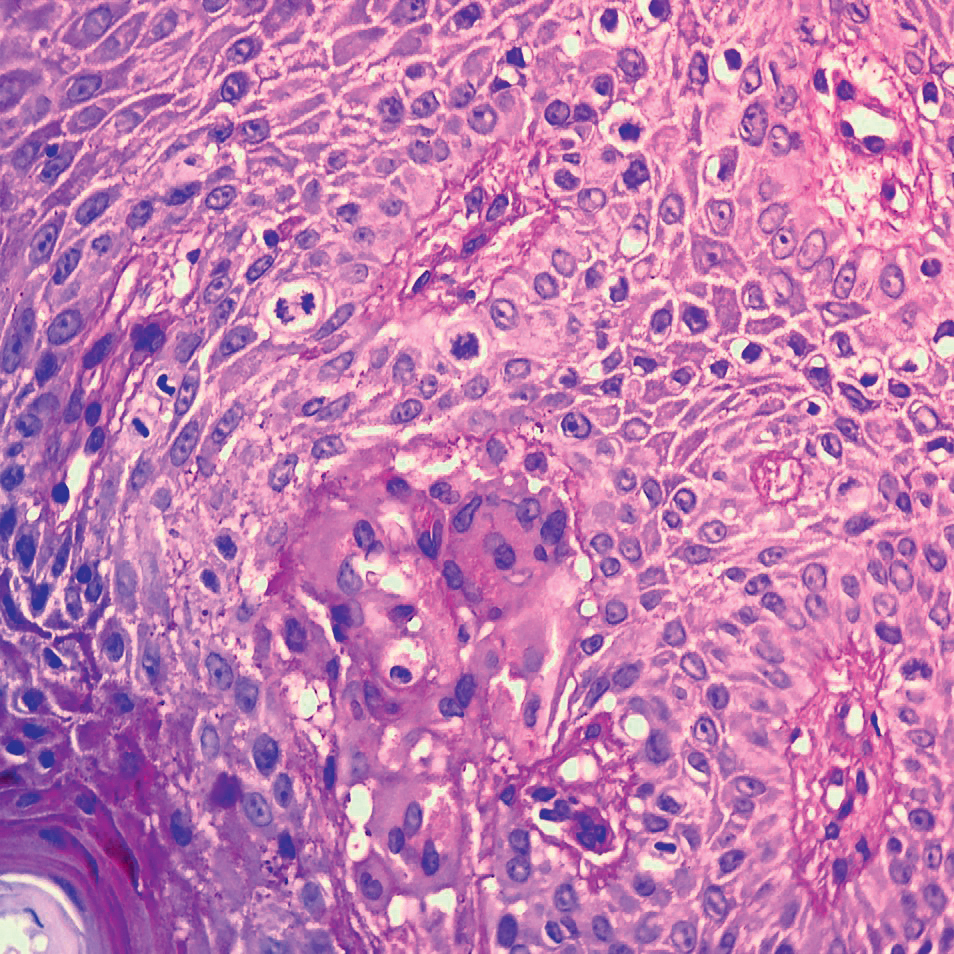

Figure 5.

A - an annular focus on the right shin measuring 3 cm in diameter, arrow 1 indicates the location of the biopsy.

B - dermatoscopic picture of rashes on the border with healthy skin.

C - histological microphotograph of skin lesion: arrows 2 indicate giant multinuclear cells, arrow 3 shows the inflammatory infiltration in subepidermal zone. Hematoxylin and eosin, x200

D - histological microphotograph of skin lesion: arrows 4 indicate giant multinuclear cells; arrow 5 shows keratin cyst with keratin layers inside. Hematoxylin and eosin, x200